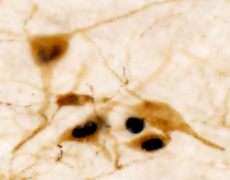

愛着行動による神経や行動の変化を明らかに

現在は、ラットやマウスを対象として、幼少期の愛着行動による大人での脳内の神経細胞や神経回路の活動変化や、幼少期に神経活動を操作した時の大人での行動変化を明らかにすることで、大人の社会性や折れない心がどの様に育まれるのか、分子・細胞レベルで明らかにすることにチャレンジしています。